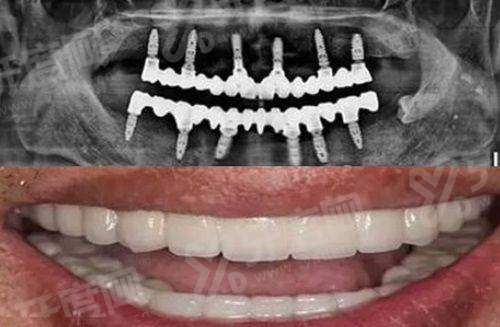

1、王浩院长有十多年的口腔临床诊疗经验,擅长种植牙、牙齿正畸、复杂牙拔除这些项目,特别多患者都是专门冲着他来的。

2、我自己去年找王浩院长做过种植牙,他会先给我做详细的口腔CT扫描,然后根据我的牙槽骨情况制定专属的种植方案,不会照搬模板。

3、治疗过程中他会随时询问我的感受,操作手法特别细致,整个过程痛感特别轻,术后修复的也比我预期的快,现在用了快一年,跟真牙没什么区别。